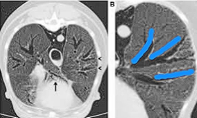

Bronchiectasis probably connected to chronic bronchitis

Can follow bronchi to the edge of the lung i.e. cylindrical bronchiestasis